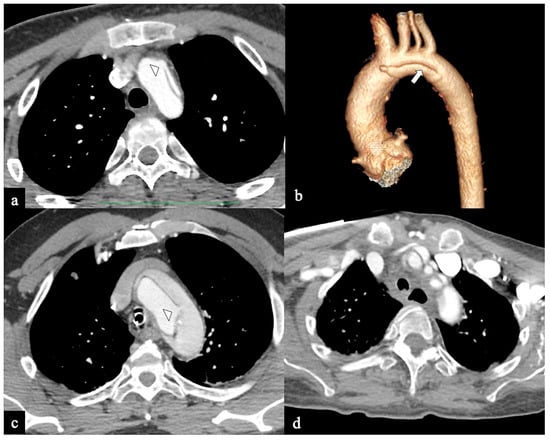

- In Configuration 3 (Arch entry), the primary ET is situated within the aortic arch, and the flap extends into the DTA without affecting the ascending aorta [38]. This Configuration 3 occurred in 7 (19%) patients (Figure 5a,b). This AD configuration was already described as proximal type B dissection according to 2010 AHA guidelines [7] and recently reported as arch B group AD from IRAD [38] and as non-A non-B acute AD with entry tear in the aortic arch [39,40]. In this configuration, the ET was often located in the greater curvature of the arch (4/6), while in one case (1/7) its location was not clearly identified. In total, 4/7 of these patients underwent hybrid and 2/7 surgical therapy.